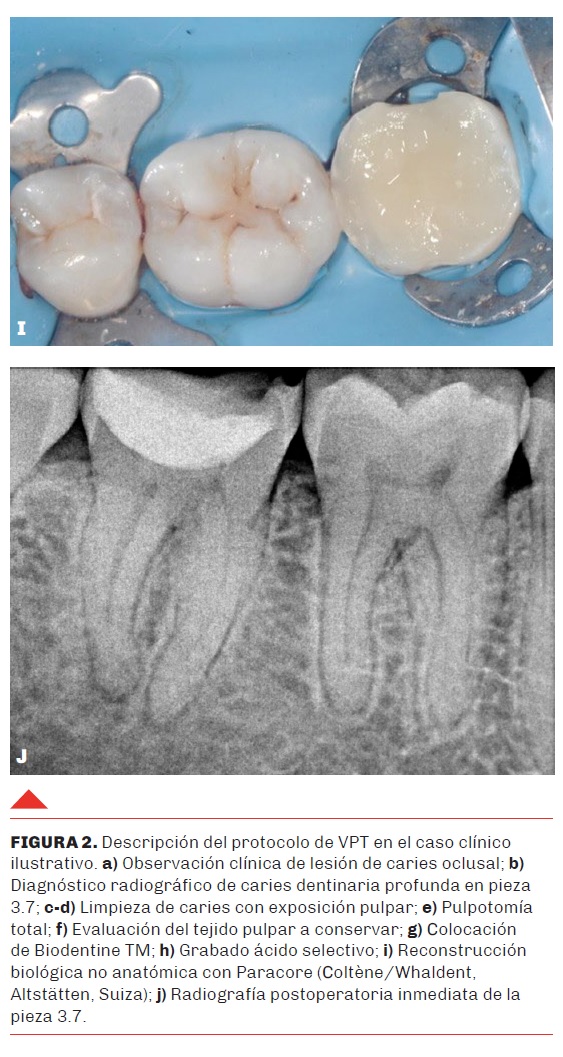

1. Anamnesis y Diagnóstico

Paciente masculino de 37 años de edad, sin antecedentes sistémicos relevantes, acude a la consulta por sintomatología dolorosa provocada ante estímulos térmicos en el cuadrante inferior izquierdo (Figura 2). Al examen clínico, se observa una lesión de caries oclusal extensa en la pieza 3.7. Las pruebas de sensibilidad térmica (frío) desencadenan un dolor agudo con ligera persistencia, mientras que las de percusión y palpación resultan negativas. Radiográficamente, se confirma una lesión radiolúcida compatible con caries dentinaria profunda con compromiso inminente de la cámara pulpar, pero con el espacio de ligamento periodontal conservado. El diagnóstico se establece como pulpitis moderada.

Se optó por una Terapia de Pulpa Vital (Pulpotomía Total) en lugar de un tratamiento endodóntico convencional, fundamentado en la capacidad regenerativa del complejo dentino-pulpar y la disponibilidad de materiales bioactivos de última generación. El objetivo primordial fue mantener la vitalidad de la pulpa radicular y aprovechar su potencial regenerativo.

Aislamiento y Acceso: Tras la administración de anestesia local, se realizó aislamiento absoluto con dique de goma y desinfección del campo con peróxido de hidrógeno al 3% y luego con clorhexidina 0,2%. Se inició la remoción de la caries dentinaria en la pieza 3.7 con una fresa de un único uso, estéril y con alta velocidad.

Abordaje Pulpar: luego de eliminar por completo la caries dental, se procedió a la escisión completa de la pulpa cameral utilizando fresas de diamante de alta velocidad bajo irrigación profusa.

Control de Hemostasia: utilizando una torunda de algodón embebida en NaOCl al 2.5%, se logró la hemostasia en un tiempo inferior a los 6 minutos, confirmando la viabilidad del tejido pulpar radicular para el procedimiento.

Protección Bioactiva: Se colocó Biodentine™ (Septodont, Francia), un cemento de silicato de calcio de alta pureza, adaptándolo sobre el remanente pulpar para garantizar su bioactividad y un posterior sellado hermético, según proporciones descritas anteriormente.

4. Restauración y Seguimiento

Tras el fraguado inicial del material bioactivo, se realizó un grabado ácido selectivo del esmalte y se procedió a una reconstrucción biológica no anatómica utilizando el sistema de resina dual ParaCoreÒ (Coltène/Whaledent AG). Este enfoque asegura un sellado coronal inmediato, factor crítico para el éxito a largo plazo.